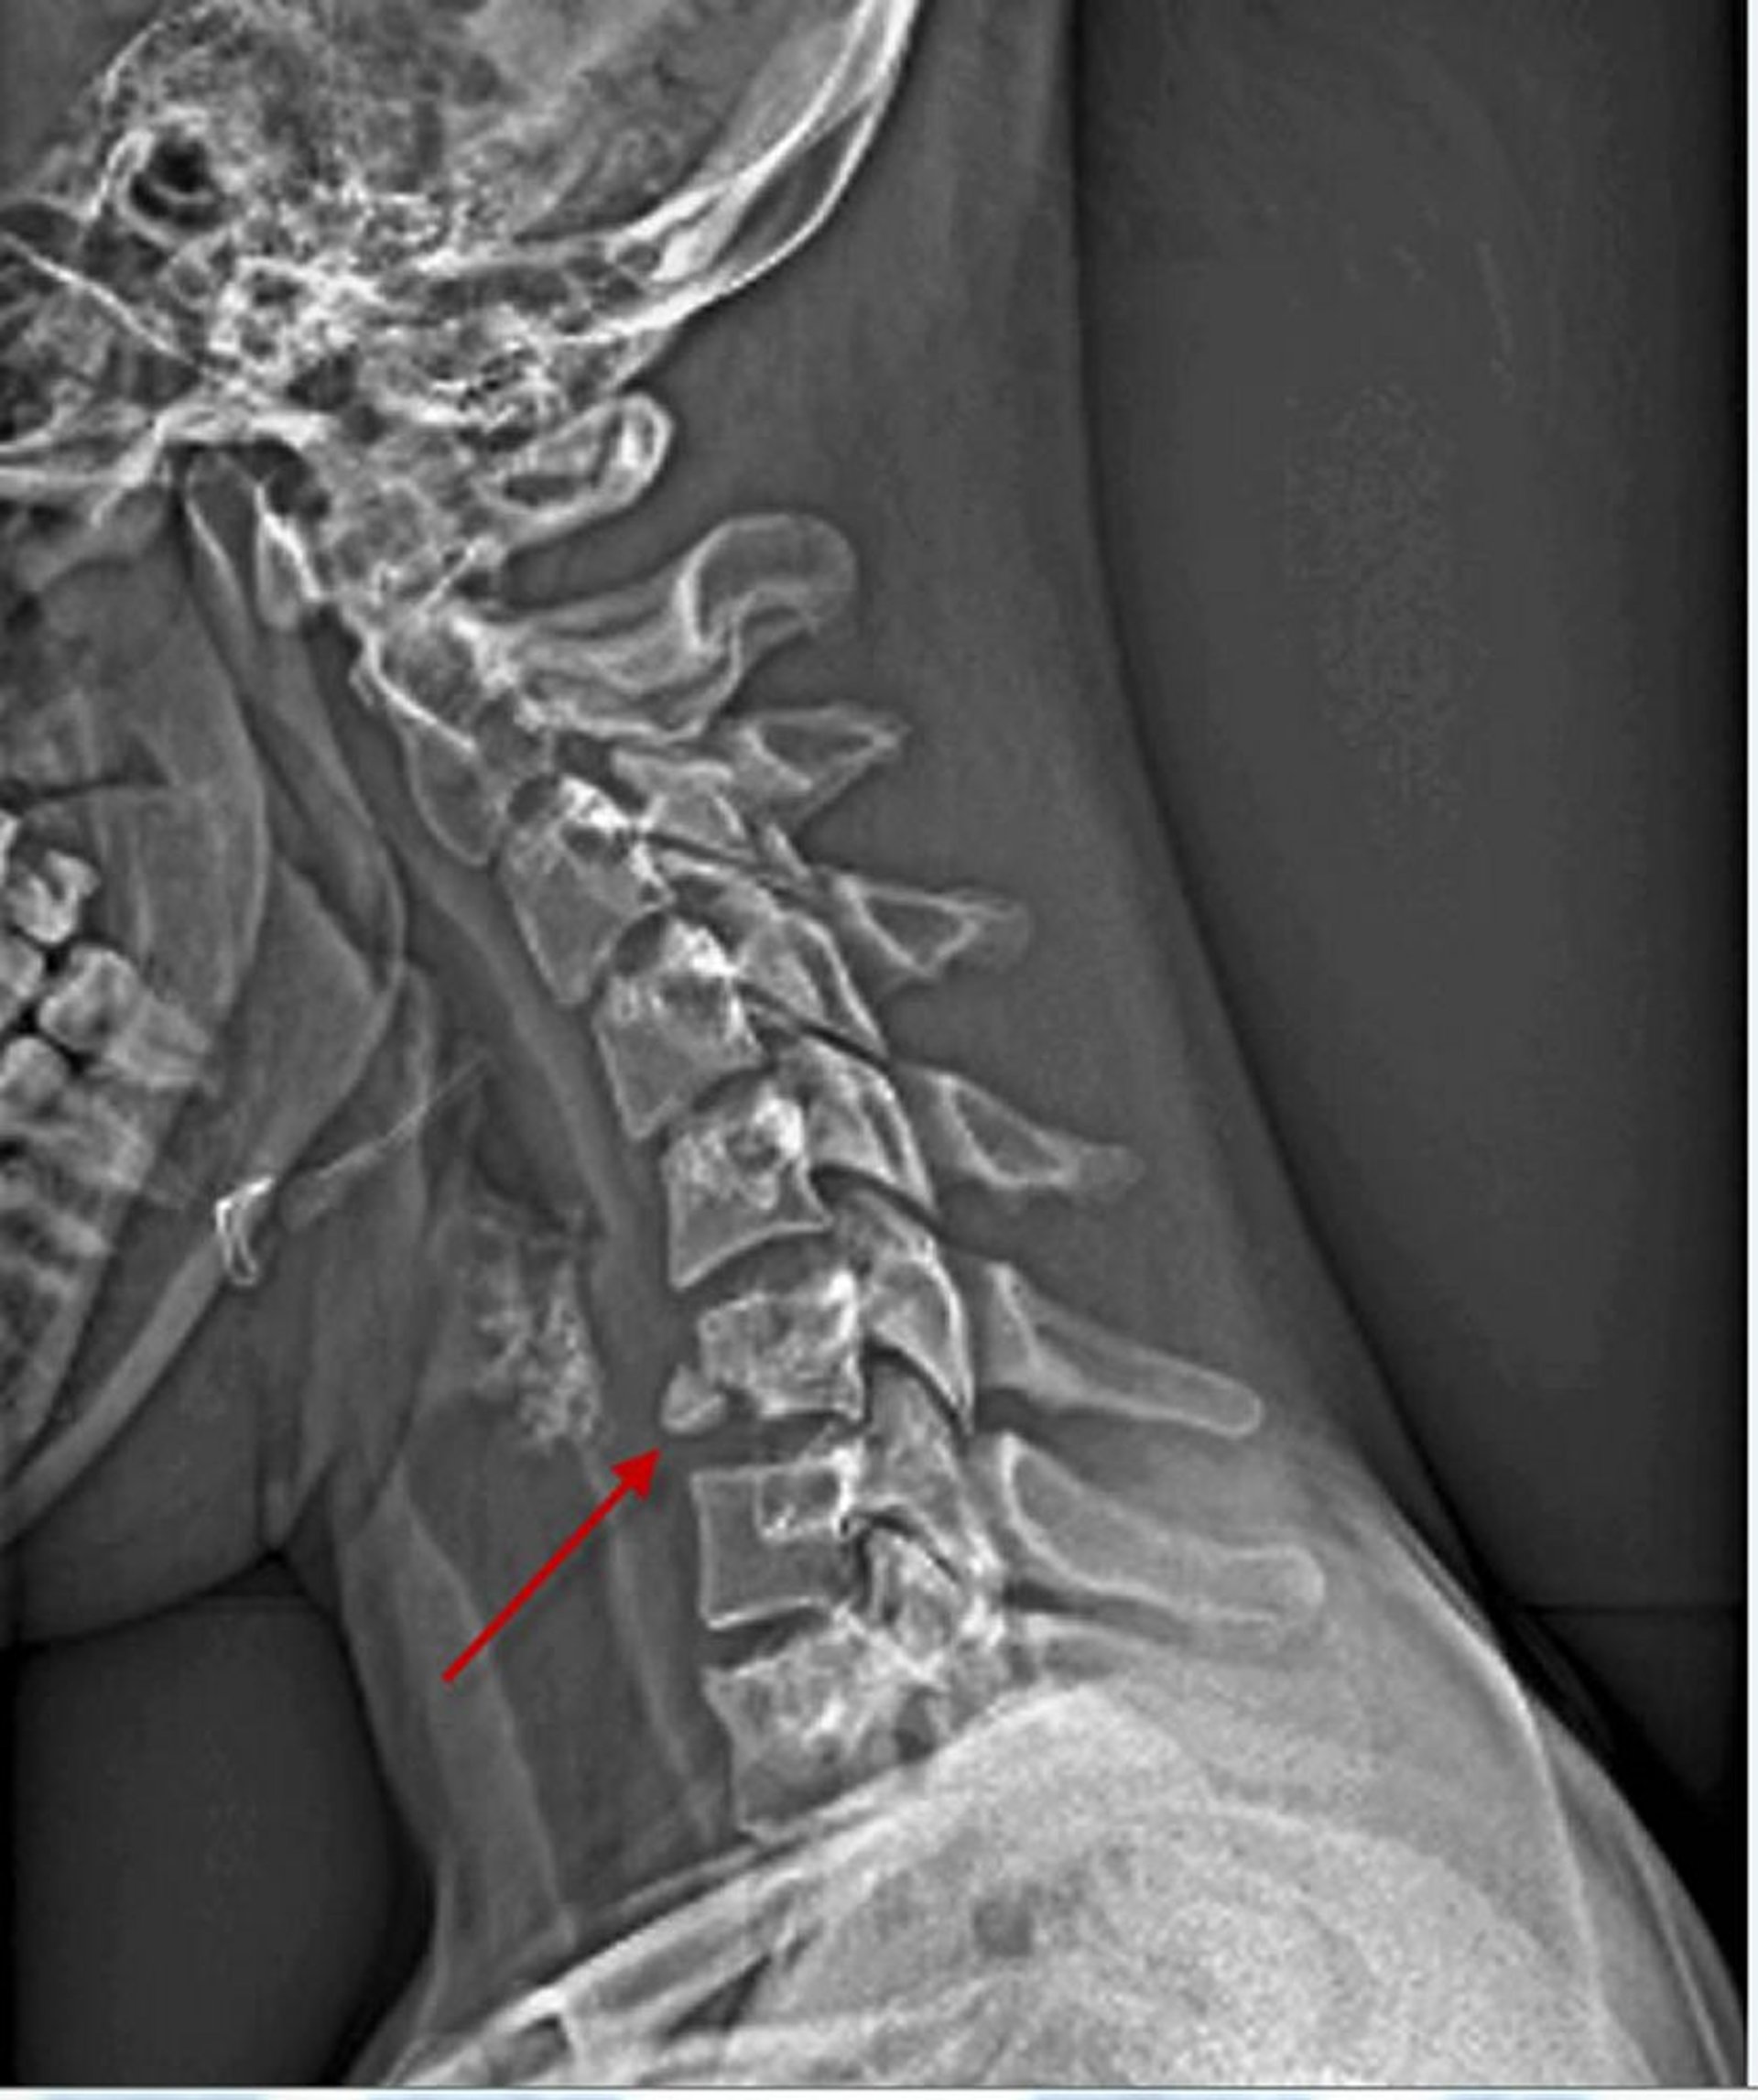

Fracture du corps vertébral cervical

Cette incidence de profil de la colonne cervicale montre une fracture de la face antérieure inférieure du 6e corps vertébral (flèche).